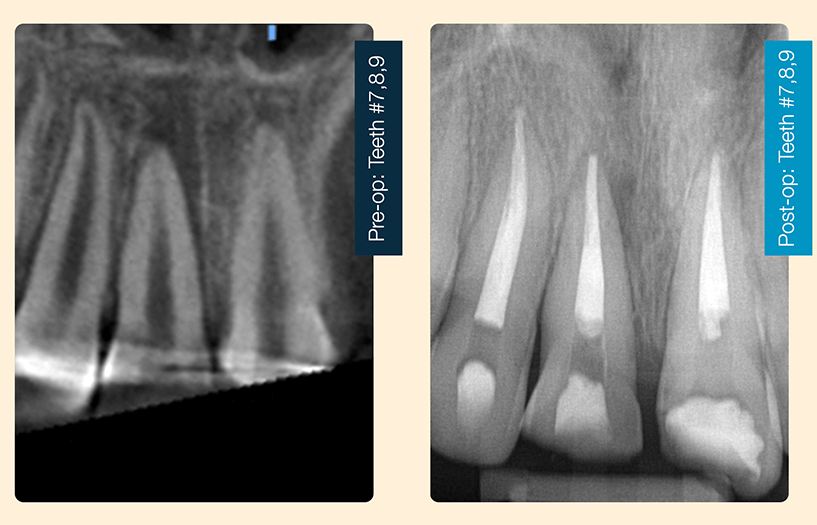

12-year-old male, trauma to front teeth at school. Tooth #8 was intruded. Teeth #8,9 pulp exposures. Tooth #7 was non-responsive to cold test and EPT. Oral surgery surgically repositioned #8 and splinted the teeth. I treated teeth #7,8,9 with 2-visit root canal therapy with 1-month calcium hydroxide. I obturated the teeth with gutta-percha and BioRoot Flow Sealer. The ease of use of the pre-mixed syringe really helped in this case because the patient had a bad experience with the splinting and was really anxious in my chair. The pre-mixed syringe saved treatment time.